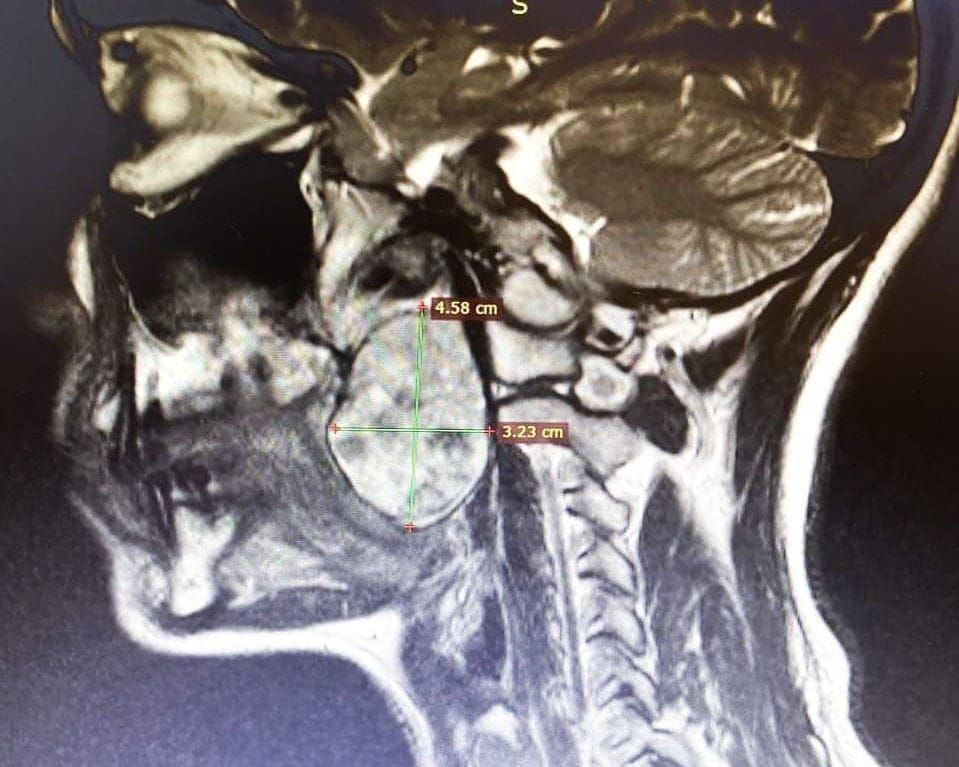

Хирурги Томской областной клинической больницы удалили у пациента новообразование в глотке размером 4×3 сантиметра. Опухоль мешала мужчине дышать, сообщает пресс-служба регионального департамента здравоохранения.

«Новообразование было удалено под общим наркозом. Пациент спасен. Опухоль была размером с небольшое куриное яйцо — размером 4,6×3,2 сантиметра. Такая патология является очень редкой», — отметил врач.